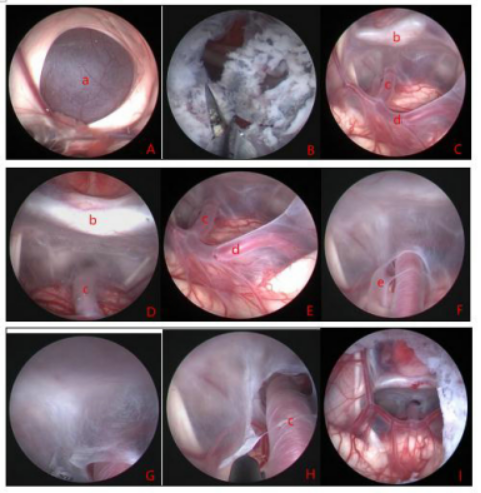

4.鞍上池囊肿(首选神经内镜手术治疗)

图8.显示鞍上囊肿伴脑积水术中所见。A:鞍上囊肿顶部; B:囊肿顶部瘘口;C、D、E:通过顶部造瘘口进入囊肿内部,可见囊肿内部的解剖结构;F:囊肿底部基底动脉旁的裂隙活瓣;G、H:囊肿底壁造瘘;I:底部造瘘完毕,从侧脑室观察上方和下方的造瘘口。A:囊肿壁 b:鞍背 c:基底动脉 d:大脑后动脉 e:裂隙活瓣